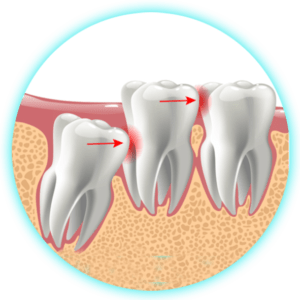

Exodoncia de Terceros Molares C/U